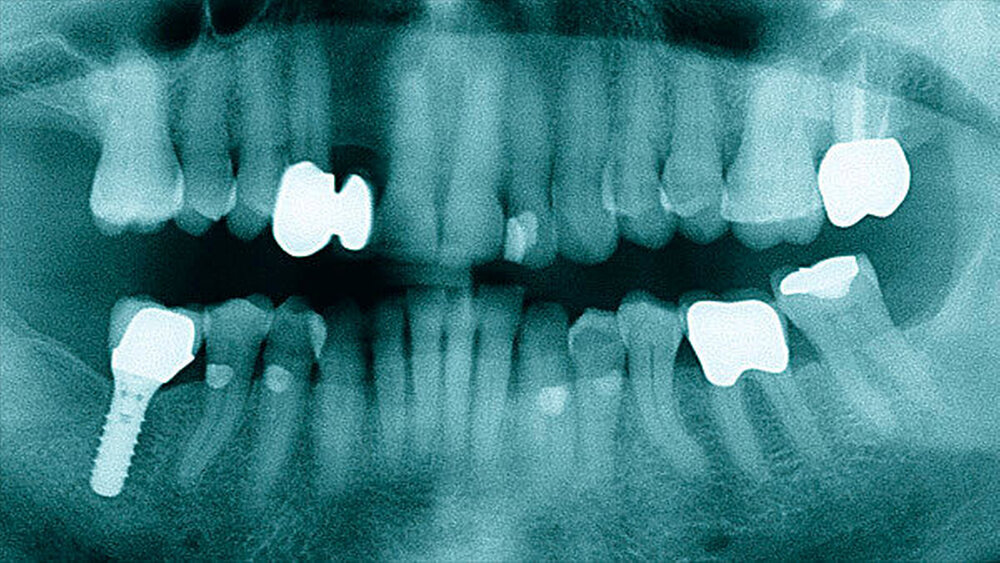

Der intraorale Befund zeigte neben einer moderat chronischen Parodontitis ein nekrotisierendes und ulzerierendes Schleimhautareal in regio 32 bis 35 (Abbildung 1). Überdies konnte eine Sondierungstiefe von 6 mm zwischen 32 und 33 sowie ein Lockerungsgrad von 1 bis 2 an den Zähnen 32 bis 34 bei positiver Sensibilität erhoben werden, wobei zumindest 2D-radiologisch kein Knochenabbau vorlag (Abbildung 2). Aufgrund des deutlich reduzierten Allgemeinzustandes des Patienten entschieden wir uns für eine stationäre Weiterbehandlung. Ein kurz darauf angefertigtes Blutbild zeigte unter anderem einen Hämoglobin-Wert von 5,2 mmol/l (Referenzbereich 8,6 bis 12 mmol/l), einen Hämatokrit-Wert von 0,24 (Referenzbereich 0,4 bis 0,51), einen Kernschatten-Wert von 40 Prozent (Referenzbereich 1 Prozent ) sowie einen CRP-Wert von 53,1 mg/l (Referenzbereich 5 mg/l).